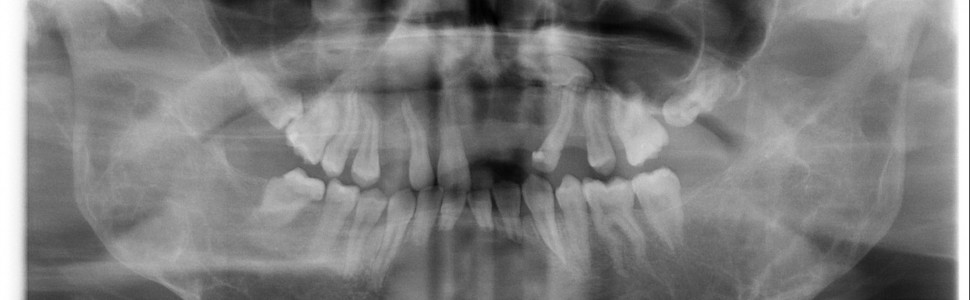

Stomatolog jako pierwszy może zauważyć nieprawidłowości w trakcie rutynowej kontroli. Zdjęcie RTG lub tomografia CBCT Wrocław pozwalają ocenić rozległość zmian kostnych.